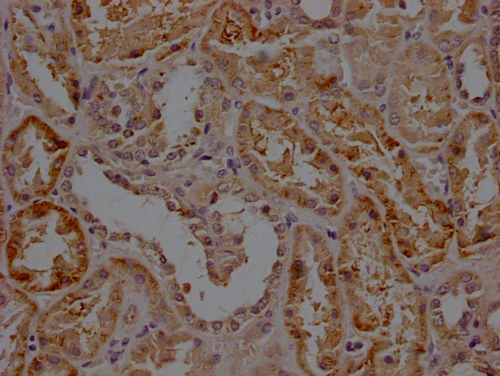

IHC image of CSB-PA744137LA11HU diluted at 1:200 and staining in paraffin-embedded human colon cancer performed on a Leica BondTM system. After dewaxing and hydration, antigen retrieval was mediated by high pressure in a citrate buffer (pH 6.0). Section was blocked with 10% normal goat serum 30min at RT. Then primary antibody (1% BSA) was incubated at 4°C overnight. The primary is detected by a Goat anti-rabbit polymer IgG labeled by HRP and visualized using 0.05% DAB.

IHC image of CSB-PA744137LA11HU diluted at 1:200 and staining in paraffin-embedded human kidney tissue performed on a Leica BondTM system. After dewaxing and hydration, antigen retrieval was mediated by high pressure in a citrate buffer (pH 6.0). Section was blocked with 10% normal goat serum 30min at RT. Then primary antibody (1% BSA) was incubated at 4°C overnight. The primary is detected by a Goat anti-rabbit polymer IgG labeled by HRP and visualized using 0.05% DAB.